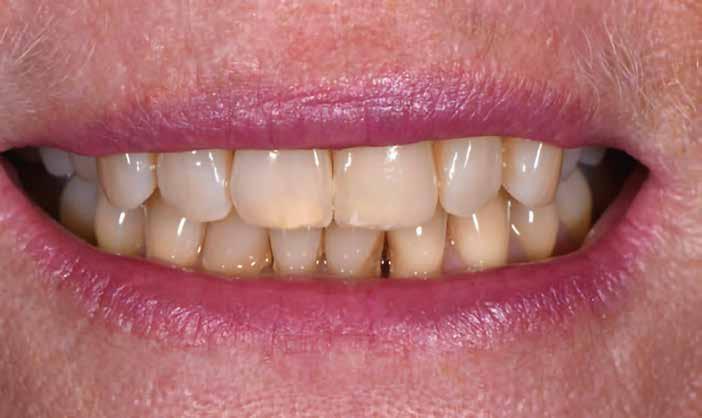

A frontfog-restauráció formáját alapvetően befolyásolja a gingiva szimmetrikus lefutása. A funkcionálisan és esztétikailag illeszkedő, bevált ideiglenesek digitális technológiával reprodukálhatók, kontúrjuk átvihető a végleges pótlásra. Ezt mutatja be két szerzőnk jelen cikkében.

1. kép: Preoperatív szituáció.

Kedvezőtlen fogállás, vagy aszimmetrikus lágyszöveti kép jelentősen megnehezíti a frontfog-rekonstrukció amúgy sem könnyű elkészítését. A forma és szín harmonikus integrációján kívül a lágyszövet formája döntő jelentőségű a természetes hatás szempontjából. Sok esetben szükséges ideiglenest készíteni, amivel a kezelőcsapat megfelelhet a gingiva biológiájának.

Pácienseset

33 éves páciens konzultált a rendelőben 3 évig tartó fogszabályozása elemeinek eltávolításáról szájából. A kárieszek eltüntetésén kívül optimalizálni szerette volna esztétikai kinézetét. Az első esztétikai elemzés a frontfogak kedvezőtlen hossz-szélesség arányát mutatta (1. kép). A bal felső szemfogat a pulpa elhalása következtében endodonciai kezelésnek is alá kellett vetni.

Tervezés

A terv a felső front rekonstrukciója volt. Anyagválasztás oldaláról figyelembe kellett venni, hogy a páciens szokásszerűen, rendszeresen fogyaszt kemény diót, ráadásul éjszaka csikorgatja a fogát (bruxizmus), és gyakran szorítja öszsze állkapcsát. A frontkoronáknak tehát esztétikus kinézet, funkcionalitás mellett kiemelkedő szakítószilárdságúnak és

nagyon erősnek kell lenniük. Hat teljes kerámiakoronával kívántuk megoldani a hossz és szélesség aránya (a fogak meghosszabbításával), és az aszimmetrikus gingivavonal optimalizálását.

Behelyezés

A fogorvos, fogtechnikus és páciens közötti jó együttműködés kifizetődik, mert a restaurációk a lehető legrövidebb idő alatt, minimális korrekcióval helyezhetők szájba. A klinikai helyzetet, amelyet a mintákon, majd az ideigleneseken keresztül idealizáltunk, a végleges restaurációval is sikerült megvalósítani (13. kép). A páciens és a kezelőcsapat elégedettsége magas szintű volt. A terápia egyenes vonalúnak, sikeresnek bizonyult.

Eredmény

Egy hónap elteltével szép, egészséges képet figyelhettünk meg, ínygyulladás nélkül (14–15. képek). A digi -